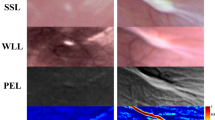

Testing SPE during transoral surgery

To further assess the reproducibility of SPE to differentiate pathologies based on contrast arising from tissue architectural changes, we further tested SPE on a patient requiring routine transoral laser surgery to remove a left glottic SCC lesion. The clinical workflow was adjusted as for the laryngectomy case, whereby SPE was tested after the routine anaesthesia for infraglottic jet ventilation and WLE inspection, and before routine transoral laser surgery. Although slight asymmetry can be observed with WLE (Fig. 5a), WLE did not reveal noticeable colour and texture contrast between the left anterior vocal cord (proven SCC by biopsy and surgical pathology) and the normal counterpart on the right. SPE revealed a suspect lesion in the left anterior vocal cord that was weakly retarding with a dark speckled appearance in the retardance image, compared to the right (Fig. 5b,c and Supplementary Video 4). This is in good agreement with the loss of retardance for cancer observed in the laryngectomy case. The anterior vocal cord on the left also presented a smaller depolarization, in comparison with the right vocal cord that was highly depolarizing (Fig. 5d,e and Supplementary Video 5). The anterior vocal cords under the different modalities have been segmented and magnified in Fig. 5f. The depolarization properties associated with normal and cancerous anterior vocal cord were fully consistent with the assessment for the laryngectomy case. The difference of the retardance and depolarization values for the cancerous and the normal anterior vocal cord is statistically significant (P < 0.001, two-sided Mann–Whitney U test) (Fig. 5g,h). The RMS contrast between the cancerous anterior vocal cord and the normal counterpart provided by SPE is much higher than that presented by WLE (Fig. 5i). Post-operative polarization microscopy confirmed the cancerous anterior vocal cord also had no LP near the tissue surface, associated with loss of retarding compositions (Fig. 5j,k), again consistent with the laryngectomy case. The posterior vocal cords showed good symmetry of shape, and similar colour, retardance and depolarization appearance by WLE and SPE, implying a consensus towards the normal status of the posterior vocal cords.

a, Larynx imaged with WLE: 1, anterior vocal cords; 2, posterior vocal cords. b,c, Retardance (b) and its intensity-reference image (c) of the larynx. d,e, Depolarization (d) and its intensity-reference image (e) of the larynx. f, Magnified images of the cancerous and normal anterior vocal cords. g,h, Retardance (g) and depolarization (h) values within the cancerous and normal anterior vocal cord. In the box plots, the red centre line denotes the median value and the blue box shows the 25th and 75th percentiles of the dataset. The black whiskers mark the non-outlier minimum and non-outlier maximum. P values were calculated via a two-sided Mann–Whitney U test for two group comparison. i, RMS contrast between the cancerous and normal anterior vocal cords in terms of retardance and depolarization revealed by the SPE and hue and saturation shown in WLE. j,k, White-light microscopy (j) and polarization microscopy (k) of the tissue slices in the left anterior vocal cord diagnosed as cancerous (SCC). Scale bar, 100 μm. For consecutive SPE imaging of this case, please refer to Supplementary Videos 5 and 6.